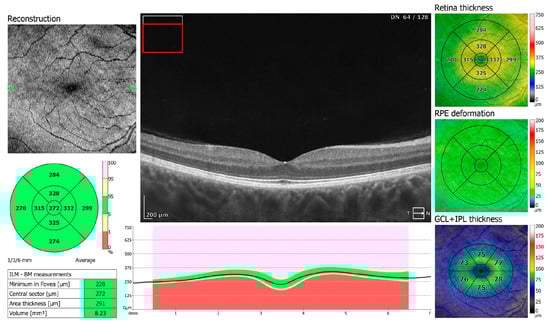

Figure 1.

OCT 3D macula scan 7 × 7 mm of COVID-19-positive patient. RPE, retinal pigment epithelium; GCL + IPL, ganglion cells layer + inner plexiform layer; ILM–BM, inner limiting membrane–Bruch’s membrane.